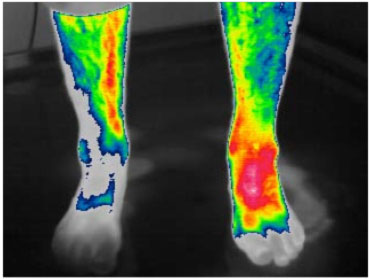

Example: human with swollen leg after surgery.

History: The photos show heat scans 4 months after surgery on the left leg. The leg was still very swollen and painful with little improvement. You can see the excess heat in red (scale in degrees Celsius). After just 2 treatments on the Vitafloor of 5 and 10 minutes each (with a 20 minute break in between), you can clearly see the drop in temperature. After several weeks of treatment this person was pain free, able to go back to work and his leg was normal again. Yet another illustration why we believe the Vitafloor to be a good tool for treating laminitis amongst other things.

Before treatment

After treatment of 5 minutes at 35 Hz.

case study

20 minutes break

After an additional 10 minutes at 35 Hz.

Heatmap of back of a persons legs